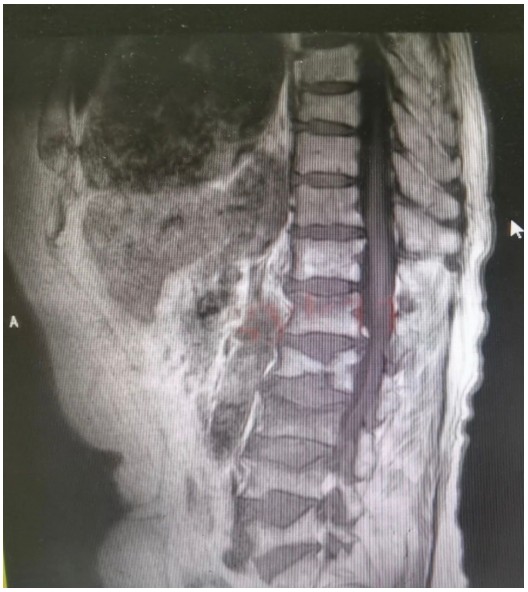

原來,89歲的占大爺因在家勞作時(shí)突發(fā)腰背部疼痛難忍、腰部無法直立,行走困難,在家臥床休息兩周后疼痛仍未減輕,于是來到衡陽市中心醫(yī)院脊柱外科就診。接診的盛凱醫(yī)師仔細(xì)查體結(jié)合磁共振檢查發(fā)現(xiàn),占大爺腰椎L1、L3、L4有椎體壓縮骨折,診斷為腰椎體壓縮骨折、重度骨質(zhì)疏松癥。錢軍博士團(tuán)隊(duì)結(jié)合對病人多椎體的骨折做出了細(xì)致的評估,經(jīng)過認(rèn)真分析研究,決定為患者實(shí)施腰椎體壓縮性骨折經(jīng)皮穿刺椎體成形術(shù)(PVP)。手術(shù)當(dāng)天,醫(yī)師團(tuán)隊(duì)在C-臂監(jiān)視器透視下,分別定位L1、L3、L4雙側(cè)椎弓根位置,以標(biāo)記穿刺點(diǎn)為中心做3mm切開,在透視下注入骨水泥,再次透視見骨水泥位置良好,順利完成手術(shù)。